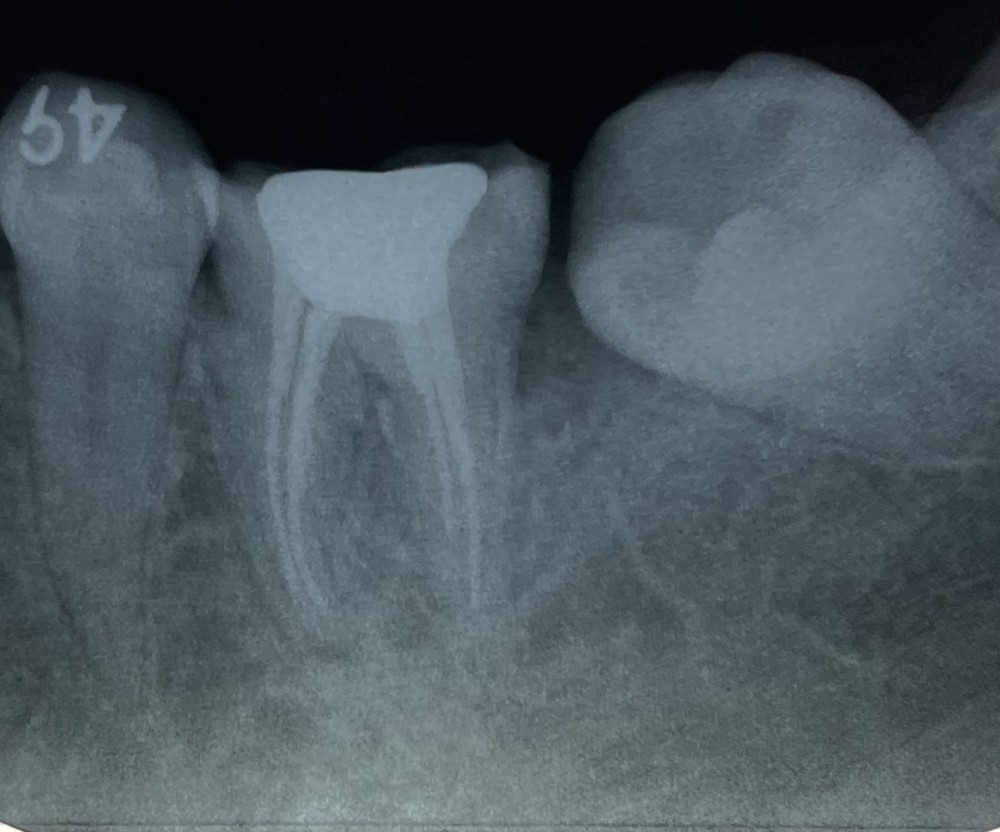

下が、根管充填の術後のエックス線写真です。

ご覧の通り、4根管あります。